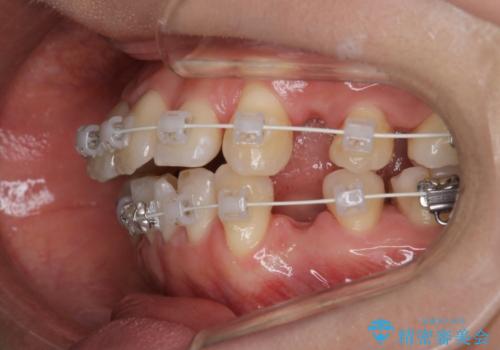

- 審美装置

- 2年2ヶ月

- 10-30回

- 上の前歯のデコボコが気になるということで来院されました。

叢生量(デコボコ)が多いため、上下左右4番目の歯を抜歯してワイヤー矯正を行う治療計画を立てました。